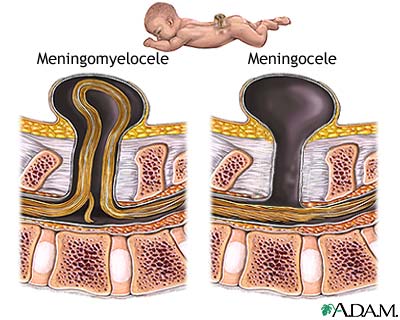

Spina bifida

(offener Rücken), Schema des Austritts des

Rückenmarks aus dem Rücken, der durch

Quecksilberdämpfe während der Schwangerschaft

begünstigt wird. Die Medizin will diesen

Zusammenhang bis heute nicht akzeptieren...